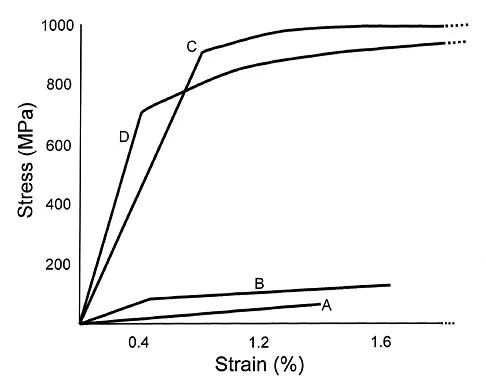

Question 18

Plots of stress versus strain for four orthopaedic biomaterials are shown in Figure 3. Referring to the figure, what is the correct identification of the curves?

Explanation